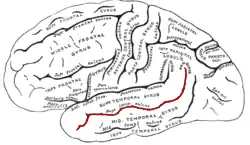

The superior temporal sulcus (STS) is the sulcus separating the superior temporal gyrus from the middle temporal gyrus, in the temporal lobe of the mammalian brain. A sulcus (plural sulci) is a deep groove that curves into the largest part of the brain, the cerebrum, and a gyrus (plural gyri) is a ridge that curves outward of the cerebrum.[1]

The STS is located under the lateral fissure, which is the fissure that separates the temporal lobe, parietal lobe, and frontal lobe.[1] The STS has an asymmetric structure between the left and right hemisphere, with the STS being longer in the left hemisphere, but deeper in the right hemisphere.[2] This asymmetrical structural organization between hemispheres has only been found to occur in the STS of the human brain.[2]